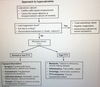

How do you workup a patient with suspected [central hypOpituitarism] (5)